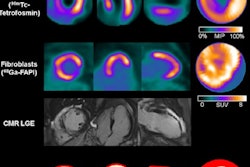

German groups appear to win the SNMMI's Image of the Year award on a regular basis, and investigators from Hannover Medical School collected this year's award.

They used a gallium-68-labeled (Ga-68) radiotracer designed to bind to fibroblast cells (Ga-68 FAPI-46) and performed fibroblast-activation protein inhibitor (FAPI)-PET imaging in 35 patients several days after they experienced a heart attack. The team found that the FAPI-PET signal in injured heart muscle predicted heart dysfunction in patients more than four months later.